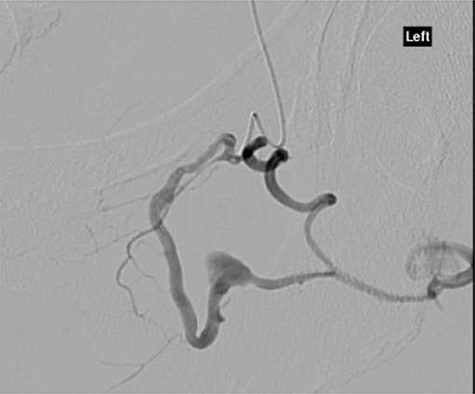

The patient was reviewed on ward around at 7:30 am by consultant orthopaedic surgeon. An urgent computed tomography (CT) angiography of the affected side was performed, as it was unclear if the haematoma was in the posterior or medial compartment; this demonstrated a large haematoma in the posterior compartment, with no cause identified (Fig. 1).

CT angiography axial slice demonstrating haematoma in posterior compartment of left thigh (white arrow).